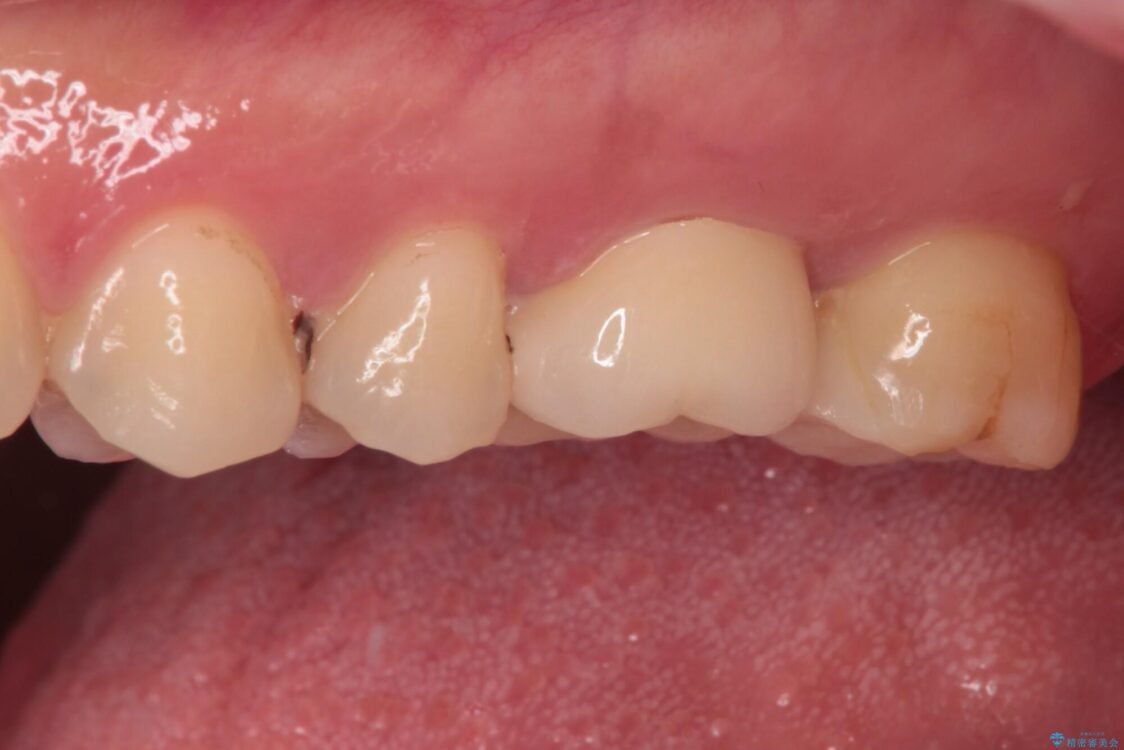

治療前

• 奥歯がズキズキと痛む 奥歯の虫歯治療 治療前画像